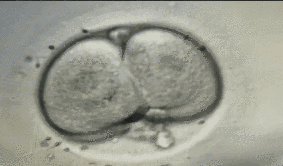

当精子与卵子在体外结合,形成受精卵后,一场神奇的细胞分裂之旅便开始了。

受精卵会从1个细胞分裂成2个,2个分裂成4个,4个分裂成8个……这个阶段的胚胎,我们称之为“卵裂期胚胎”。

通常情况下,我们会对受精后的第3天(D3)胚胎进行第一次“海选”评估。

这次海选,评委(胚胎学家)主要通过显微镜观察,像评选“最美证件照”一样,从外观形态上给胚胎打分。这套评分系统主要依据以下三个核心指标: